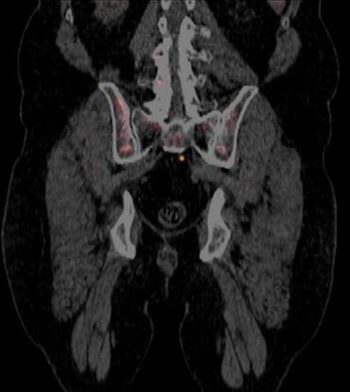

Called Axumin, the agent is intended for PET imaging of men who are suspected of having recurrent prostate cancer, based on elevated prostate-specific antigen (PSA) levels that occur after primary treatment. Axumin contains a fluciclovine amino acid labeled with an F-18 radioisotope.

In its regulatory submission for Axumin, Blue Earth provided results from two clinical studies evaluating the safety and efficacy of the radiopharmaceutical. In the first study of 105 men with suspected recurrent prostate cancer, the results of Axumin scans were compared with histopathology and biopsy. Radiologists interpreted the scans onsite initially, and then three independent, blinded radiologists read the scans.

In the second study, researchers evaluated the agreement between Axumin scans and studies acquired with another PET radiopharmaceutical, choline-11, in patients with median PSA values of 1.44 ng/mL. Again, onsite radiologists read the scans, and then the same three independent radiologists from the first study read the Axumin scans.